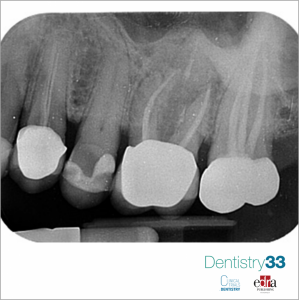

Female patient, 65 years old, requested a visit for widespread pain in the second quadrant, particularly localized in the molar area.The intraoral periapical examination (Fig. 1) reveals bone...

Authors: Prof. Dr. Daniele Cardaropoli, Dr. Alessandro Roffredo

Second of 3 clinical cases in which three-dimensional radiology has allowed us to avoid making diagnostic errors otherwise not evaluable with two-dimensional radiography alone.